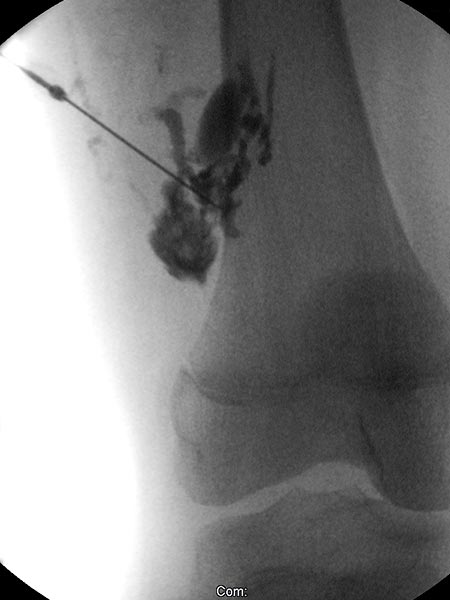

Digital subtraction angiography after direct puncture of the venous malformation during sclerotherapy. In addition to the lesion, direct communicating veins with the deep conducting vein system are visible. These were occluded with viscous alcohol gel by direct puncture.

X-ray fluoroscopy after direct puncture of the venous malformation during sclerotherapy. As a result of closure of the communicating veins to the deep venous system, the VM is now isolated and can be sclerosed. After injection of contrast, no outflow of the contrast medium into the deep veins.